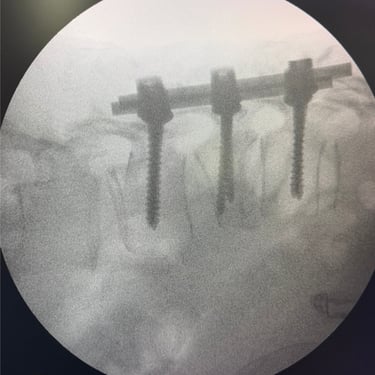

Fractura vertebral lumbar – Artrodesis con tornillos transpediculares (FTP).

La fractura vertebral lumbar es una lesión que puede comprometer la estabilidad de la columna y generar dolor, deformidad o déficit neurológico. En casos seleccionados, el tratamiento quirúrgico mediante artrodesis con tornillos transpediculares (FTP) permite una fijación firme de las vértebras afectadas, restaurando la alineación y brindando estabilidad inmediata. Esta técnica reduce el dolor, previene el desplazamiento vertebral y protege las estructuras neurológicas. La intervención oportuna, junto a una adecuada rehabilitación, favorece una recuperación funcional segura y mejora significativamente la calidad de vida del paciente.